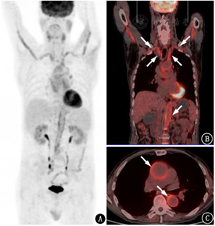

18F-FDG PET/CT除用于肿瘤性疾病外,也是炎性疾病诊断和评估的重要方法。18F-FDG PET/CT可以评价大动脉炎/巨细胞动脉炎患者受累血管壁的代谢情况,有时可以意外诊断大动脉炎/巨细胞动脉炎[1]。在不明原因发热的患者中,18F-FDG PET/CT可能发现尚未诊断的大动脉炎/巨细胞动脉炎,从而明确发热的原因(图2)。一般而言,18F-FDG PET/CT对大动脉炎/巨细胞动脉炎的诊断性能较好,诊断灵敏度为80%~90%,特异性为73%~98%[2]。但用该方法评估大动脉炎/巨细胞动脉炎时,需要注意以下问题。